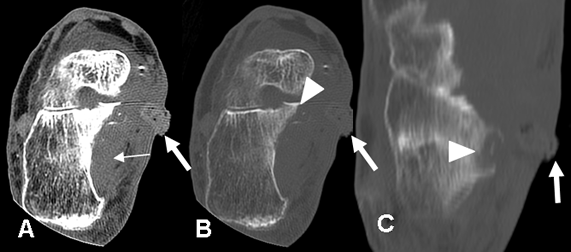

Fig 65. Osteomielitis del calcáneo.

A: TAC axial en ventana de tejido y B: en ventana de hueso. Cambios inflamatorios en los tejidos blandos (Flecha delgada), con orificio de fístula medial. (Flecha gruesa).

C: TAC reconstrucción coronal. Erosión del calcáneo, por osteomielitis. (Punta de flecha).